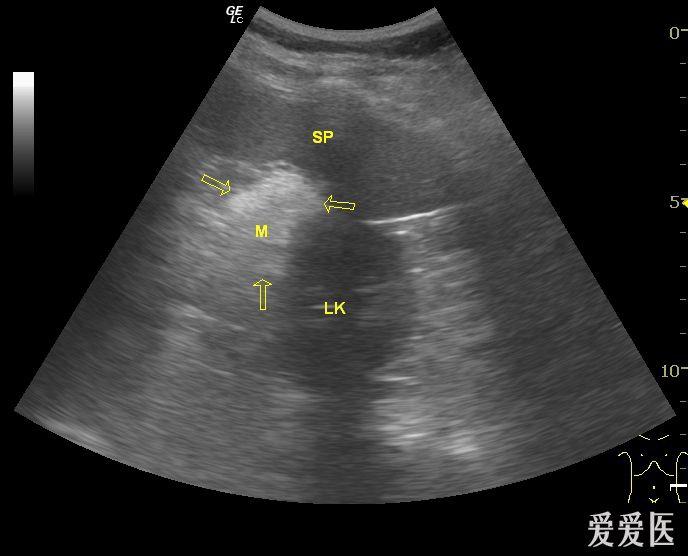

以上箭头所示为脾切迹.

查:体温38.3℃,wbc:15×109/l,触诊左中上腹压痛,b超提示脾